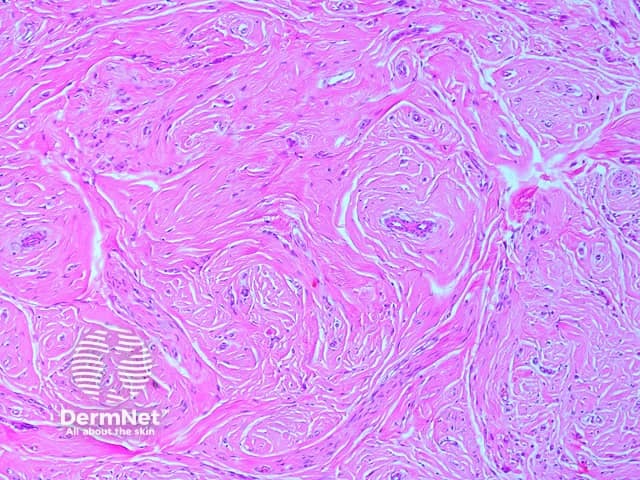

Microscopic examination of angiomyofibroblastoma demonstrates a well-circumscribed tumour without a capsule and with variable cellularity. Hypocellular areas are collagenous (figure 1) or myxoid with some small-medium sized vessels. Hypercellular areas, located predominately around the vessels, contain characteristic plump round/oval shaped cells with relatively uniform nuclei without remarkable atypia (figure 2). Occasional multinucleated and binucleated cells may be seen.

Figure 1